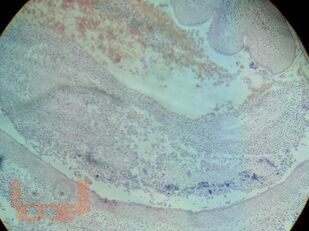

В учебном пособии «Патологическая анатомия критических состояний» на современном уровне изложена актуальность изучения клинической патологической анатомии. Освещены принципы современной патоморфологической диагностики, основы работы с нормативной документацией, принципы построения патологоанатомического диагноза, что заложено в освоении современных общепрофессиональных и профессиональных компетенций в подготовке врача. Приведенные клинические примеры посмертной патоморфологической диагностики с описанием гистопрепаратов, обозначением структурных изменений, оформлением образцов нормативной документации делают информацию более доступной и запоминающейся, формируя основы клинического мышления и клинико-анатомического анализа на особенностях патоморфогенеза заболеваний, что заложено в основе российской патологоанатомической школы.